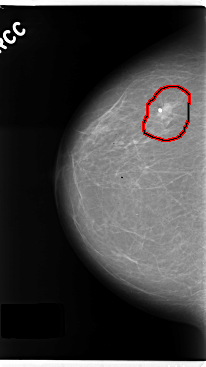

FILE: C_0190_1.RIGHT_CC.OVERLAY

TOTAL_ABNORMALITIES 1

ABNORMALITY 1

LESION_TYPE CALCIFICATION TYPE ROUND_AND_REGULAR DISTRIBUTION CLUSTERED

LESION_TYPE MASS SHAPE OVAL MARGINS SPICULATED

ASSESSMENT 5

SUBTLETY 5

PATHOLOGY MALIGNANT

TOTAL_OUTLINES 1

BOUNDARY